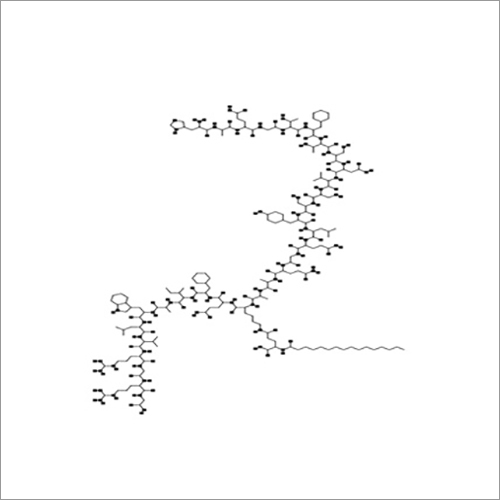

| रासायनिक नाम | Thymopentin |

| रासायनिक नाम | Thymopentin |